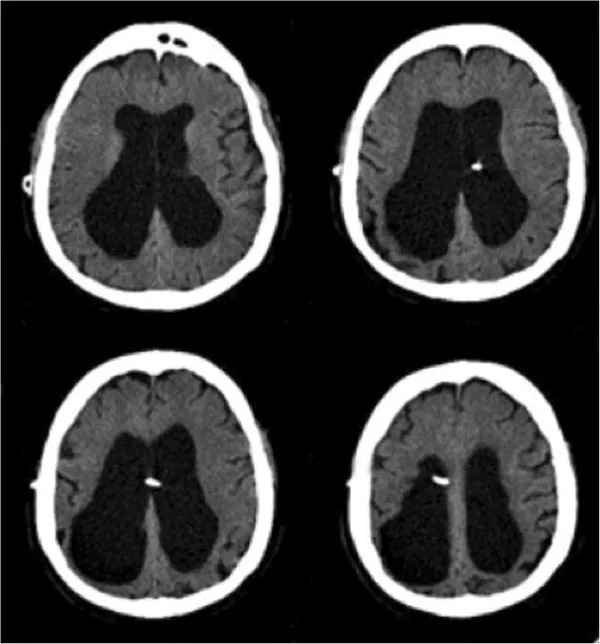

- Normal pressure hydrocephalus (triad: dementia, gait apraxia, incontinence)

- Chronic subdural haematoma

- Neuroimaging: MRI brain (or CT if contraindicated)

- Vascular (20%): Stepwise decline, stroke history, white matter changes